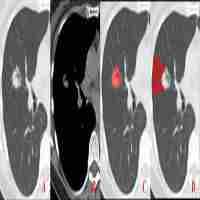

| Abstract | AbstractLymph nodes (LN) metastasis differentiation from computed tomography (CT) images is a challenging problem. This study aims to investigate the association between radiomics image parameters and LN metastasis in colorectal mucinous adenocarcinoma (MAC).Clinical records and CT images of 15 patients were included in this study. Among them, 1 patient was confirmed with all metastatic LNs, the other 14 were confirmed with all non-metastatic LNs. The regions of the LNs were manually labeled on each slice by experienced radiologists. A total of 1054 LN regions were obtained. Among them, 164 were from metastatic LNs. One hundred nine image parameters were computed and analyzed using 2-sample t test method and logistic regression classifier.Based on 2 sample t test, image parameters between the metastatic group and the non-metastatic group were compared. A total of 73 parameters were found to be significant (P < .01). The selected shape parameters demonstrate that non-metastatic LNs tend to have smaller sizes and more circle-like shapes than metastatic LNs, which validates the common agreement of LN diagnosis using computational method. Besides, several high order parameters were selected as well, which indicates that the textures vary between non-metastatic LNs and metastatic LNs. The selected parameters of significance were further used to train logistic regression classifier with L1 penalty. Based on receiver operating characteristic (ROC) analysis, large area under curve (AUC) values were achieved over 5-fold cross validation (0.88 ± 0.06). Moreover, high accuracy, specificity, and sensitivity values were observed as well.The results of the study demonstrate that some quantitative image parameters are of significance in differentiating LN metastasis. Logistic regression classifiers showed that the parameters are with predictive values in LN metastasis, which may be used to assist preoperative diagnosis. |